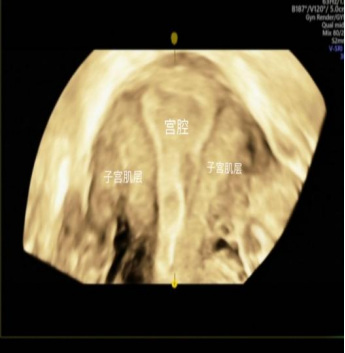

是在宫腔内放入子宫造影管,然后推入造影剂,造影剂会沿着双侧的输卵管流入盆腔,通过超声显象动态观察输卵管是否通畅,输卵管的走形、子宫形态以及宫内的占位、病变等情况。